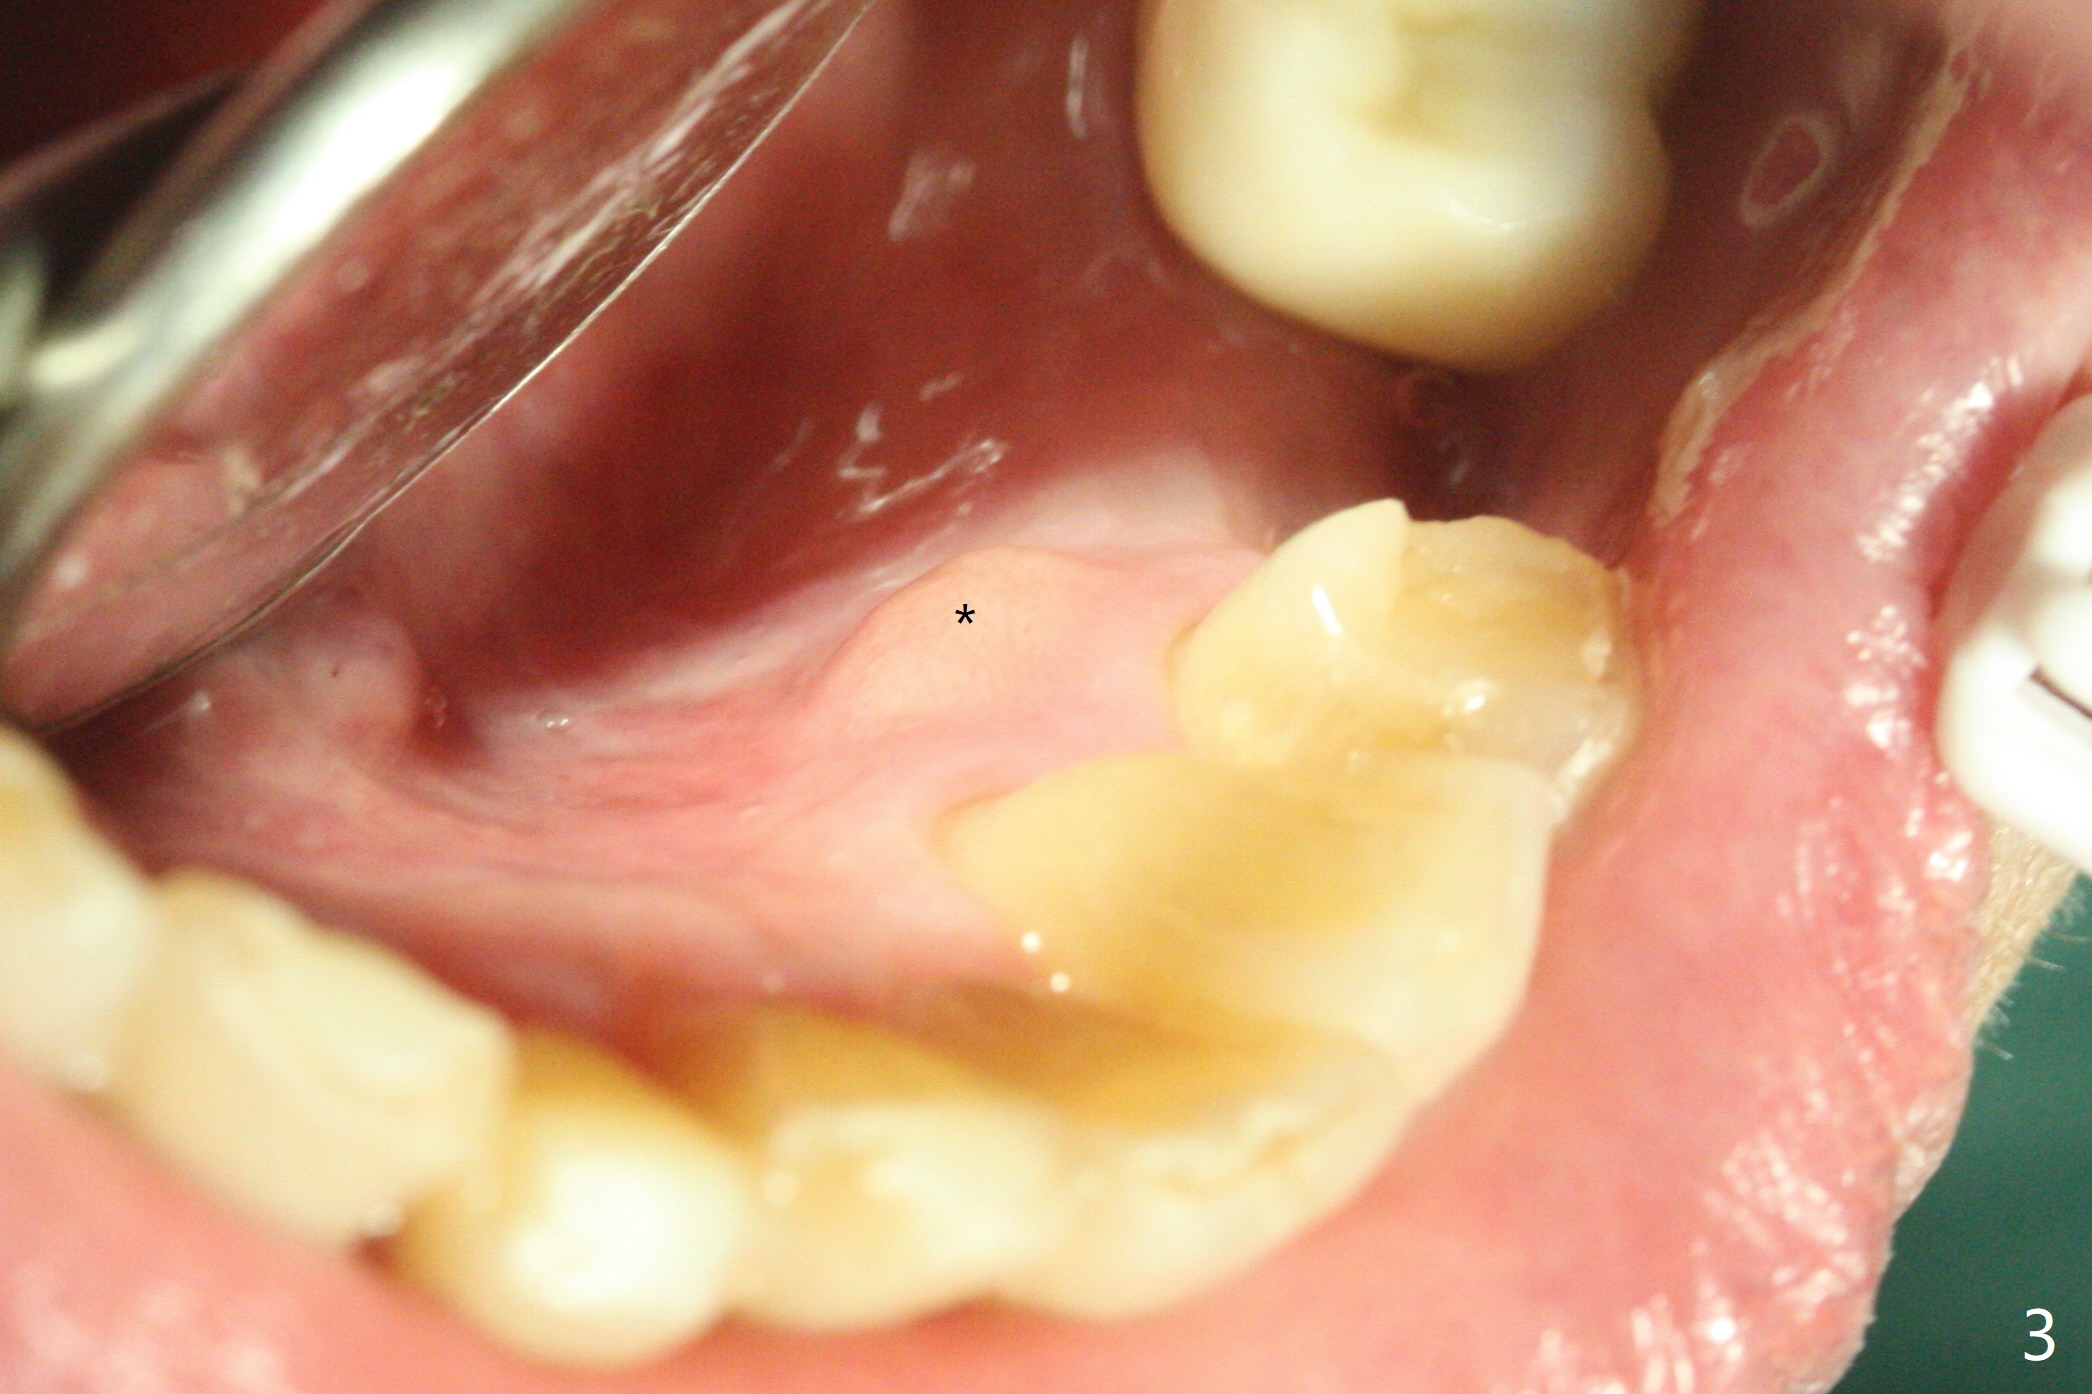

A 73-year-old man with history of stroke presented to office with #20 chewing pain 2 years ago (Fig.1). When he returns today, the tooth #20 has lost, while #21 has mobility (Fig.2), torus mandibularis (Fig.3 *) and severe bone loss, as related to Class V defect (Fig.4). As expected, the buccal plate is lost, the buccal gingiva blanching and bulging due to a curette underneath (Fig.5 *). After placement of allograft in the socket (Fig.6,8 *), a 8x8 mm BioXclude and 4-0 PGA suture are used to close the socket (Fig.7). Periodontal dressing stays in place 10 days postop (Fig.9). The patient is pleased with hemostasis. He is going to return his home state.